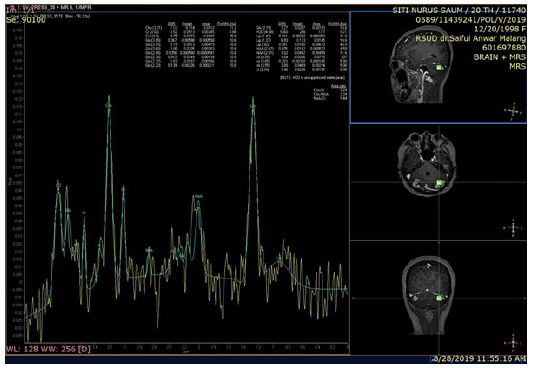

Physical examination showed a good patient consciousness with GCS of 456, right hemiparese with the upper limb and lower limb power were 2 and 4 respectively, and presence of smelly yellowish discharge in both ears. Weber test showed no lateralization and Rinne was negative. The discharge culture result showed colony of Pseudomonas aeruginosa sensitive with gentamycin, ceftazidime, and meropenem, but resistance to ciprofloxacin and levofloxacin. The discharge Ziehl Neelsen test and Gene expert result showed negative result. Sputum gene expert result also showed negative result. Chest X ray and sputum examination gen expert didn’t detect tuberculosis infection (Figure 1). Head contrast MRI showed multiple lesions in cerebellum, right parietal lobe, and left occipital lobe accompanied by cerebral edema, suggestive of cerebral abscess (Figure 2). We have given intravena antibiotik for management of cerebral abscess for 14 days but there is no clinical improvement, we performed head MR spectoscopy and suggested cerebral tuberculosis with increased lactate, NAA degradation, and increased choline/creatine ratio in lesion (Figure 3). The administration of HRZS (Isoniazid, Rifampicin, pyrazinamide, streptomycin) oral anti tuberculosis therapy according to the guidelines for intracranial TB therapy gave satisfactory results with clinical and radiological improvement.

When ring enhancement lesion is found in CT scan or MRI, MR spectroscopy has high diagnostic value for diagnosing tuberculoma. MR spectroscopy will show high lipid concentration, reduced NAA and creatinine concentration, and creatinine/choline ration >1. The high lipid concentration in MR Spectroscopy along with the ring enhancement lesion are specific for tuberculoma and are not seen in any differential diagnosis for tuberculoma. MR Spectroscopy can also distinguish tuberculoma and bacterial tuberculosis abscess. In TB abscess, MR Spectroscopy will show a high level of lactate and significant acetate presentation [6].

MR Spectroscopy result showed isointenseT1W1 intraaxial lesion, hyper intense T2W1/FLAIR at non restricted central DWI, some with SWI blooming, Multiple in the right and left cerebellum hemisphere and in the right parietal lobe subcortex which worsen the rim after contrast administration. The largest diameter was 8.2 mm in right cerebellum hemisphere. There was lipid degradation, increased lactate, NAA degradation, and increased choline/ creatine ratio in lesion, compared to the perilesion tissue. Furthermore, multiple intraaxial lesions were found in bilateral cerebellum hemisphere and right sub cortex suspected with tuberculoma (improved), bilateral chronic mastoiditis (fixed) (Figure 2).

In normal brain, MR Spectroscopy will show the predominant N-acetylaspartate (NAA), choline, creatine, and myo-inositol with highest spectrum on NAA. NAA is neuronal marker for healthy tissue, choline shows energy deviation and is cellular marker [6].